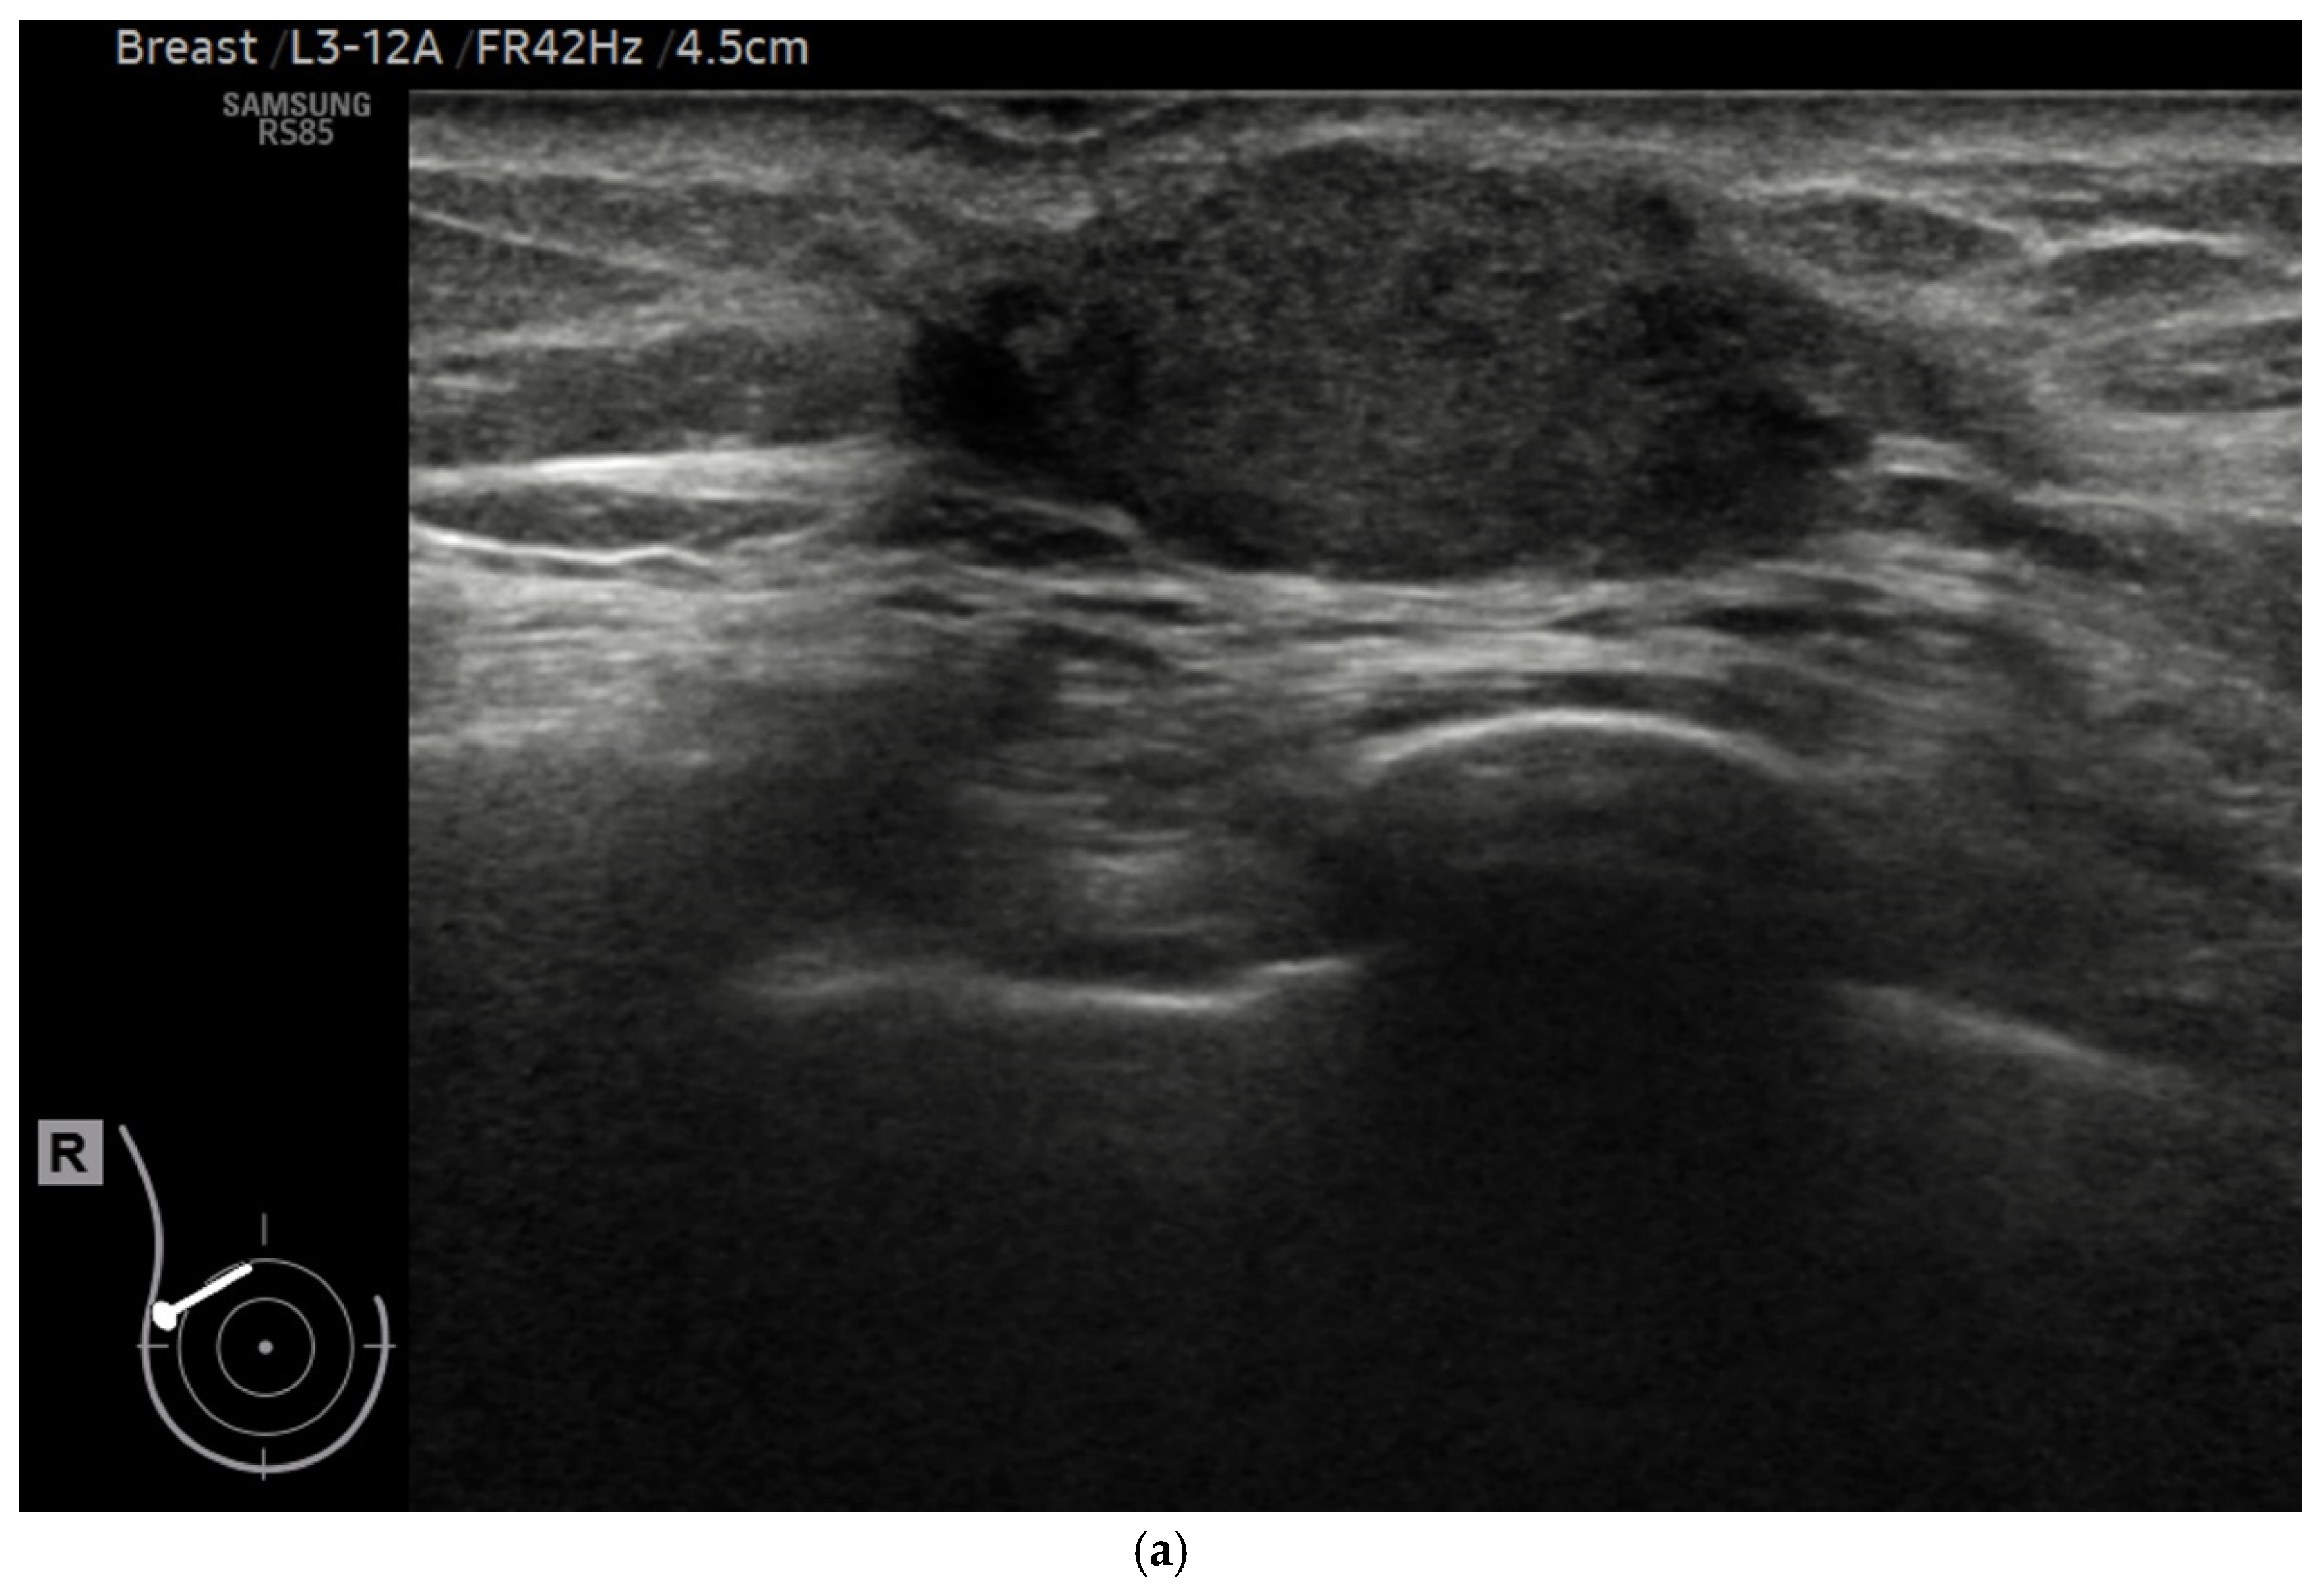

2.2. Ultrasound Procedure

2.4. AI Analysis